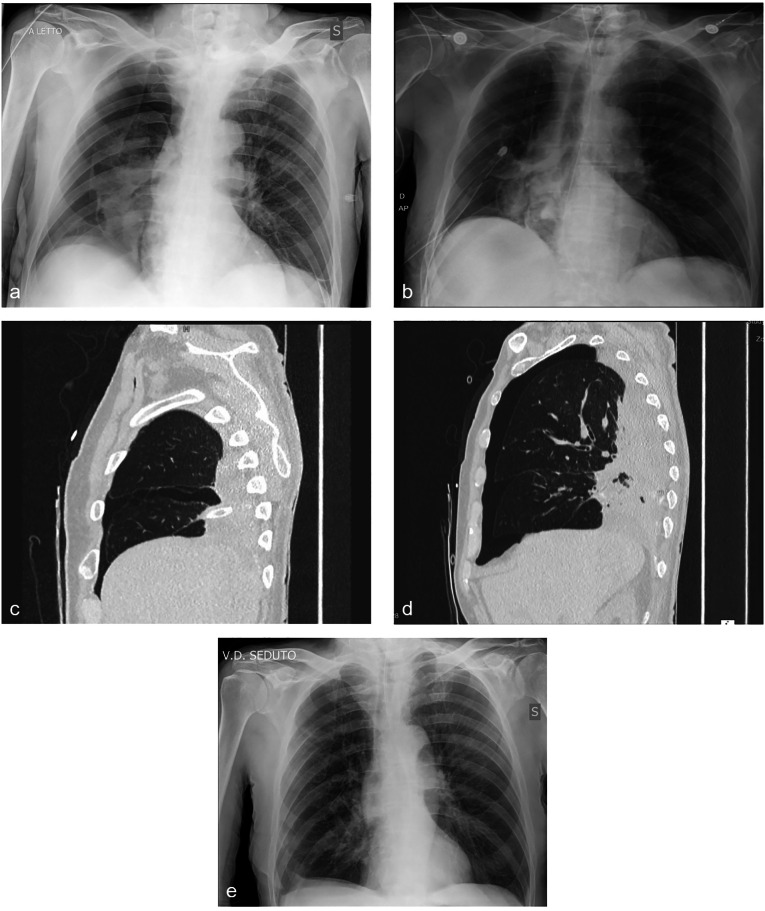

气胸的定义是胸膜腔中存在空气,是一种潜在的危及生命的疾病,需要及时诊断和量身定制的治疗。快速准确的诊断主要是通过放射成像来实现的。气胸的治疗策略因其严重程度和病因而异。保守护理,包括警惕观察和补充氧气,适用于小的,稳定的气胸。针吸可能是有效的一线治疗,尽管在某些情况下可能会失败,需要升级。流动设备方便门诊护理,缩短住院时间。胸腔引流仍然是一种基础疗法。在选择性病例中可实施留置胸膜导管。支气管内治疗,包括瓣膜和导管,为减少空气泄漏的流量提供了微创选择。医学胸腔镜与滑石粉粉末提供诊断和治疗的好处,病人不适合手术,而手术干预是最终治疗的黄金标准。对于不适合手术的患者,辅助干预包括滑石粉浆液胸膜固定术和自体血贴片胸膜固定术。有效的管理需要个性化的治疗计划,包括风险因素调整、疼痛管理和物理治疗。这种实用的方法旨在更新读者的治疗方式,可用于所有形式的气胸在临床实践中。

Pneumothorax, defined by the presence of air in the pleural cavity, is a potentially life-threatening condition requiring prompt diagnosis and tailored management. Rapid and accurate diagnosis is primarily achieved through radiological imaging. Management strategies for pneumothorax vary according to severity and aetiology. Conservative care, involving vigilant observation and supplemental oxygen, is suitable for small, stable pneumothoraxes. Needle aspiration can be an effective first-line treatment, although it may fail in some instances, necessitating escalation. Ambulatory devices facilitate outpatient care and reduce the length of hospital stays. Chest drainage remains a cornerstone therapy. Indwelling pleural catheters may be implemented in selective cases. Endobronchial treatments, including valves and spigots, offer minimally invasive options for reducing the flow of air leaks. Medical thoracoscopy with talc poudrage provides both diagnostic and therapeutic benefits in patients unsuitable for surgery, while surgical intervention represents the gold standard for definitive treatment. Adjunctive interventions include talc slurry pleurodesis and autologous blood patch pleurodesis for patients unsuitable for surgery. Effective management necessitates individualized treatment plans, incorporating risk factor modification, pain management, and physiotherapy. This practical approach aims to update the reader on the treatment modalities that can be used in all forms of pneumothorax in clinical practice.